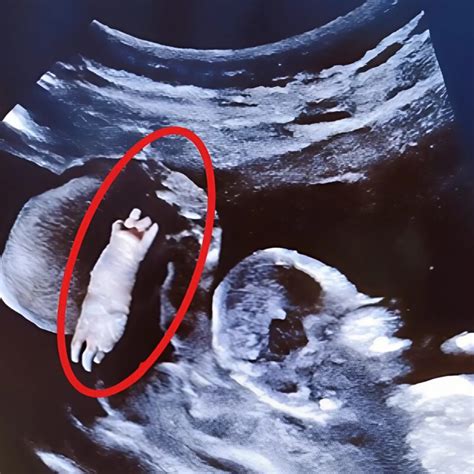

4D echoskopija žengia dar toliau, nes ji sujungia 3D vaizdus į trumpą filmuką. Tai reiškia, kad galima stebėti ne tik statinius vaisiaus atvaizdus, bet ir jo judesius realiu laiku - kaip jis spardosi, vartosi, mojuoja rankytėmis ar net bando apsiversti. Ši technologija leidžia išsamiai apžiūrėti vaisiaus veidą, rankas, kojas ir stebėti jo aktyvumą.

- III trimestras (nuo 26-32 sav. iki 41 sav.): Toliau vertinama vaisiaus būklė, placentos ir virkštelės kraujotaka, vandenų kiekis. Šiuo laikotarpiu (ypač 26-32 sav.) 3D ultragarsu galima aiškiai matyti realius vaikelio veido bruožus, daromos 3D nuotraukos ir video įrašai. Tokie susitikimai su kūdikiu suteikia ypatingą artumo ir pažinimo jausmą.